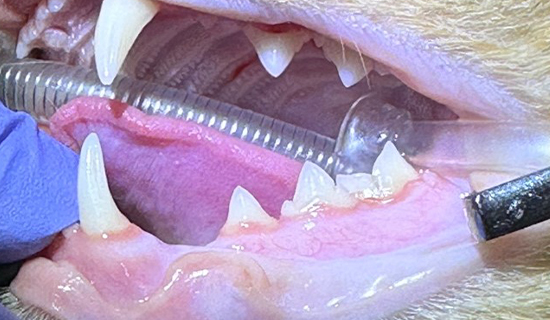

정상 치아의 모습과 치아엑스레이 영상

치아흡수병변의 모습과 치아엑스레이 영상(Type1)